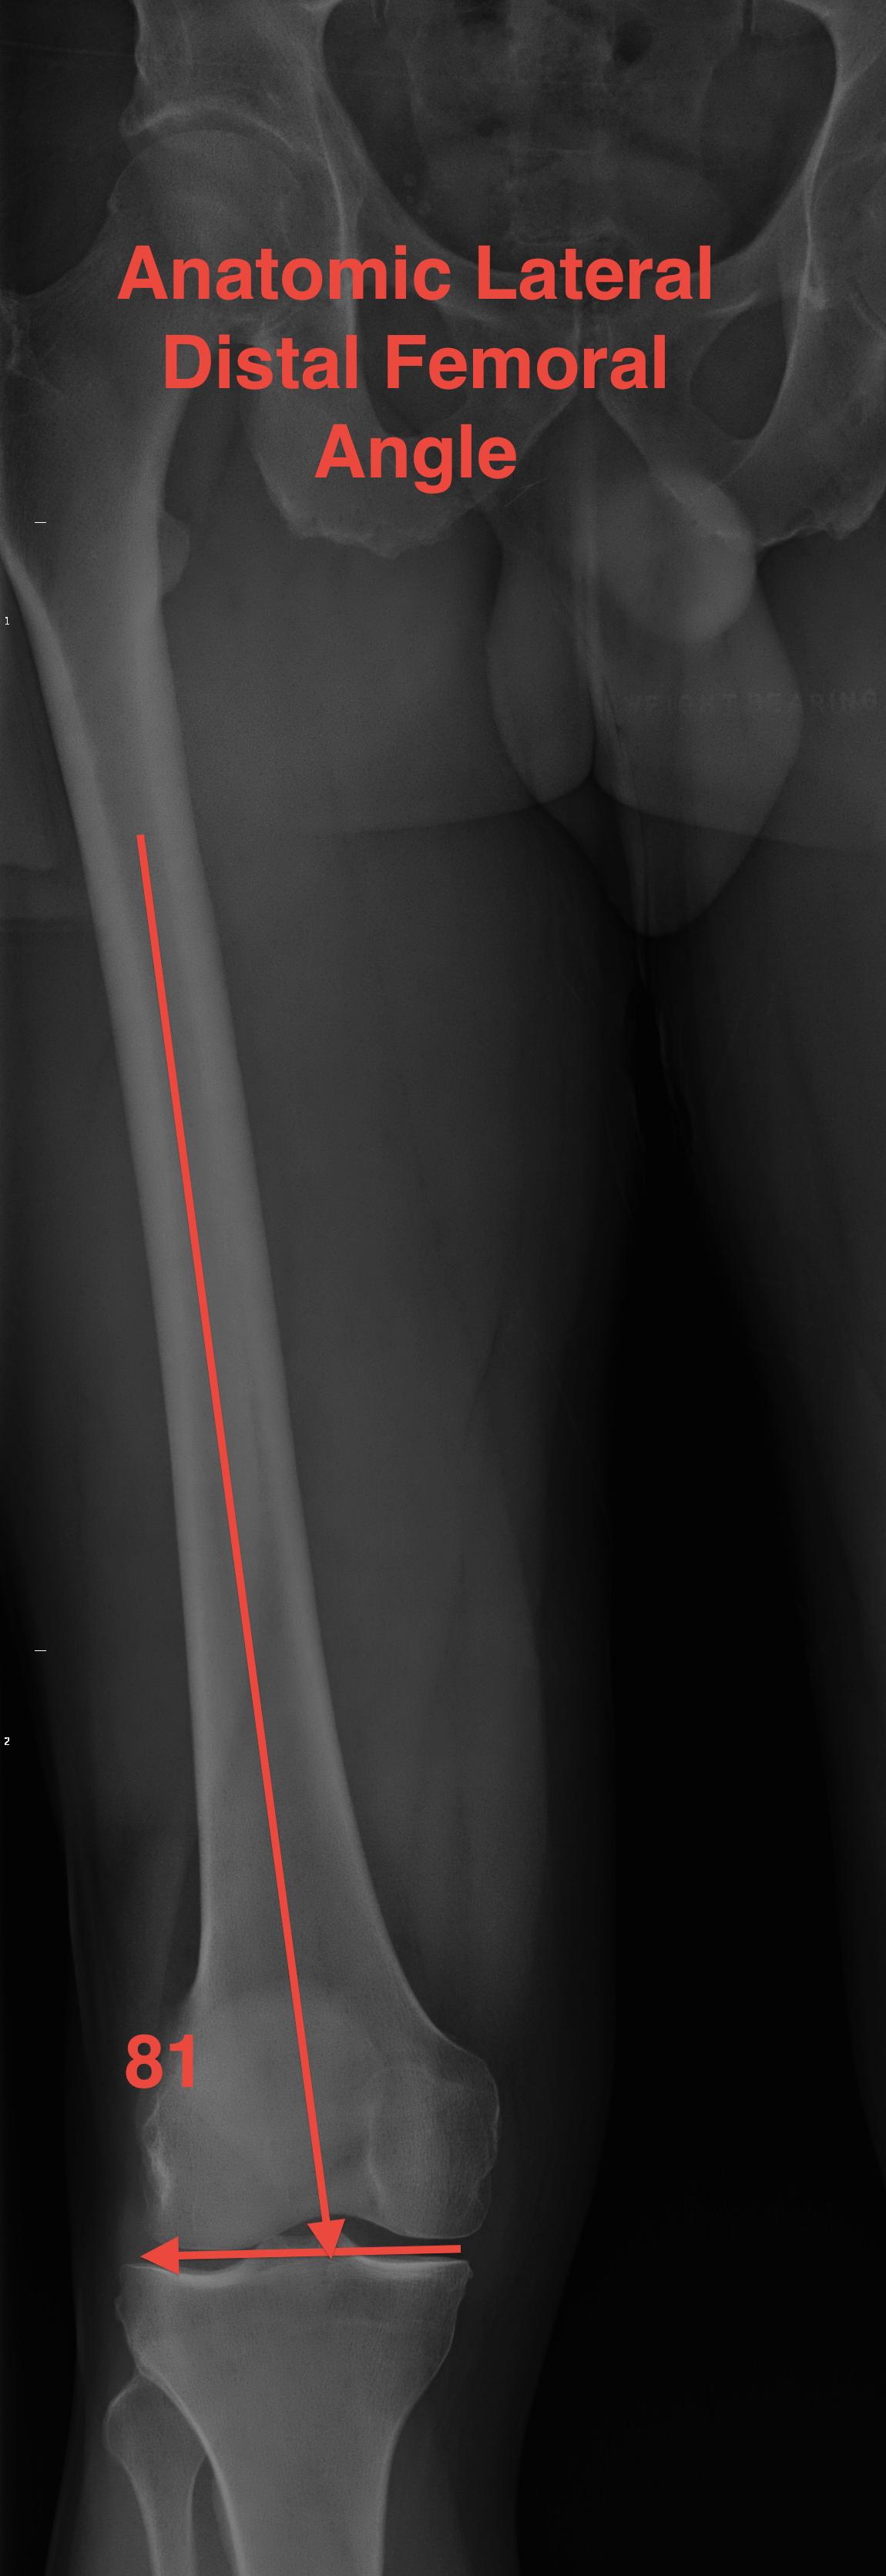

aLDFA (anatomical Lateral Distal Femoral Angle) |

| 3o valgus relative to MA | 81o | 87o | 87o or 3o varus | 9° |

| 6o valgus distal femur | ||||